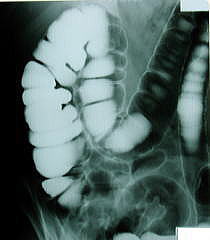

病院に搬送され後に、医師から見せられた腹部のレントゲン写真を見て、声が出なかったそうです。

なんと便とガスで腸で真っ白だったんです。

善玉元気を飲んで、腸内改善して、すっきりとした気持ちでレントゲン結果を見てみましょう!

肌荒れトラブルや痩せにくい体、そして恐ろしい真っ白なレントゲン写真と決別!